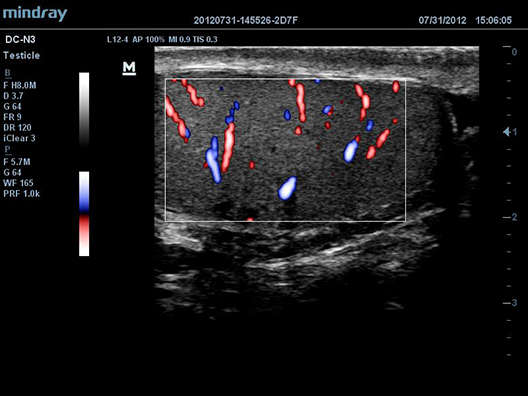

DC-N3

–£–ó-—Å–∫–∞–Ω–µ—Ä DC-N3 –ø—Ä–µ–¥—Å—Ç–∞–≤–ª—è–µ—Ç —Å–æ–±–æ–π –æ–ø—Ç–∏–º–∞–ª—å–Ω–æ–µ —Å–æ—á–µ—Ç–∞–Ω–∏–µ –∫–∞—á–µ—Å—Ç–≤–∞, —É–Ω–∏–≤–µ—Ä—Å–∞–ª—å–Ω–æ—Å—Ç–∏ –∏ –¥–æ—Å—Ç—É–ø–Ω–æ—Å—Ç–∏ –∏ —è–≤–ª—è–µ—Ç—Å—è –Ω–∞—Å—Ç–æ—è—â–∏–º –ø–µ—Ä–µ–æ–ø—Ä–µ–¥–µ–ª–µ–Ω–∏–µ–º –æ—Å–Ω–æ–≤, –æ–±–µ—Å–ø–µ—á–∏–≤–∞—è –ª—É—á—à—É—é –≤ —Å–≤–æ–µ–º –∫–ª–∞—Å—Å–µ —Ñ—É–Ω–∫—Ü–∏–æ–Ω–∞–ª—å–Ω–æ—Å—Ç—å –∏ —ç—Ñ—Ñ–µ–∫—Ç–∏–≤–Ω–æ—Å—Ç—å –ø–æ —Ä–∞–∑—É–º–Ω–æ–π —Ü–µ–Ω–µ.